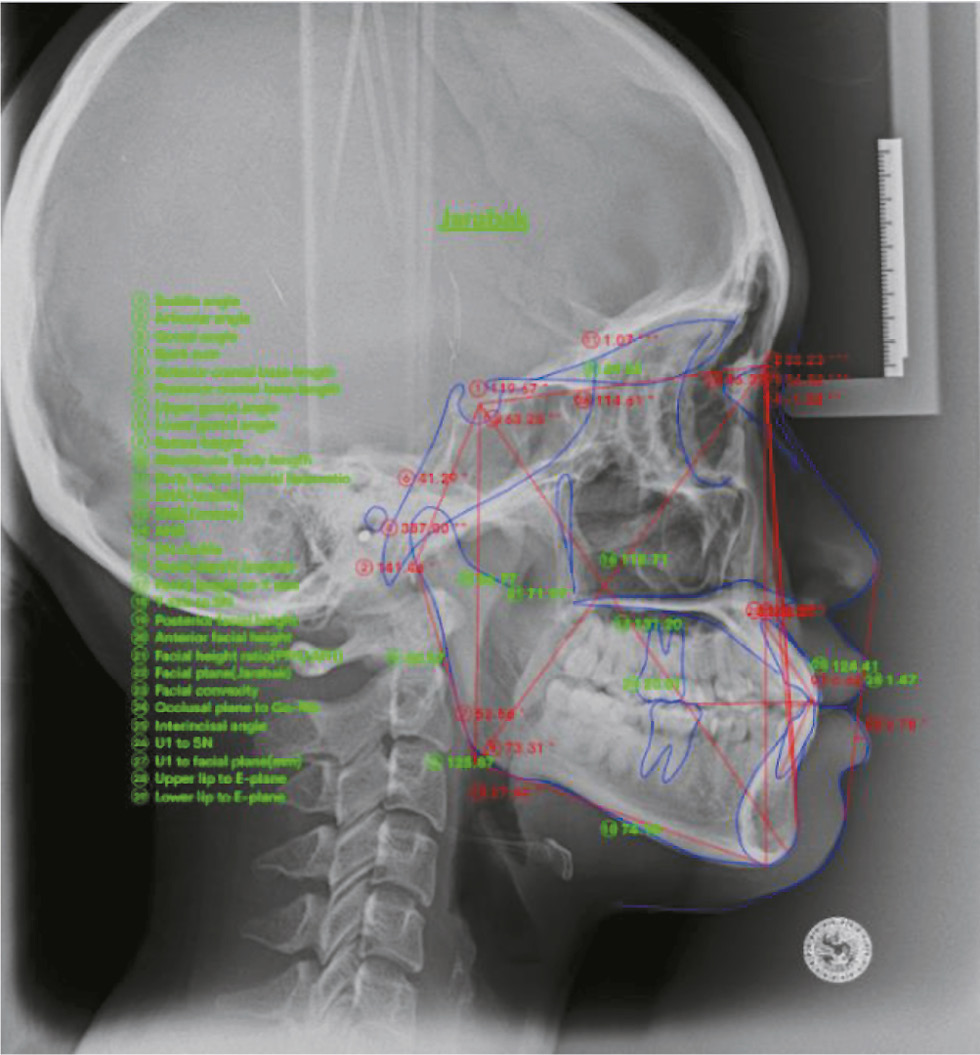

The ANN cephalometric parameters were measured using the end web application, which is a medical record application for orthodontic care. This application is utilized because of its cost-free nature and its capability to reduce errors associated with manual procedures. The visual representation of the measurement obtained using the front-end web application is depicted in Fig. 1.

Fig. 1. Analysis of cephalometric parameters using the front-end web application [13].